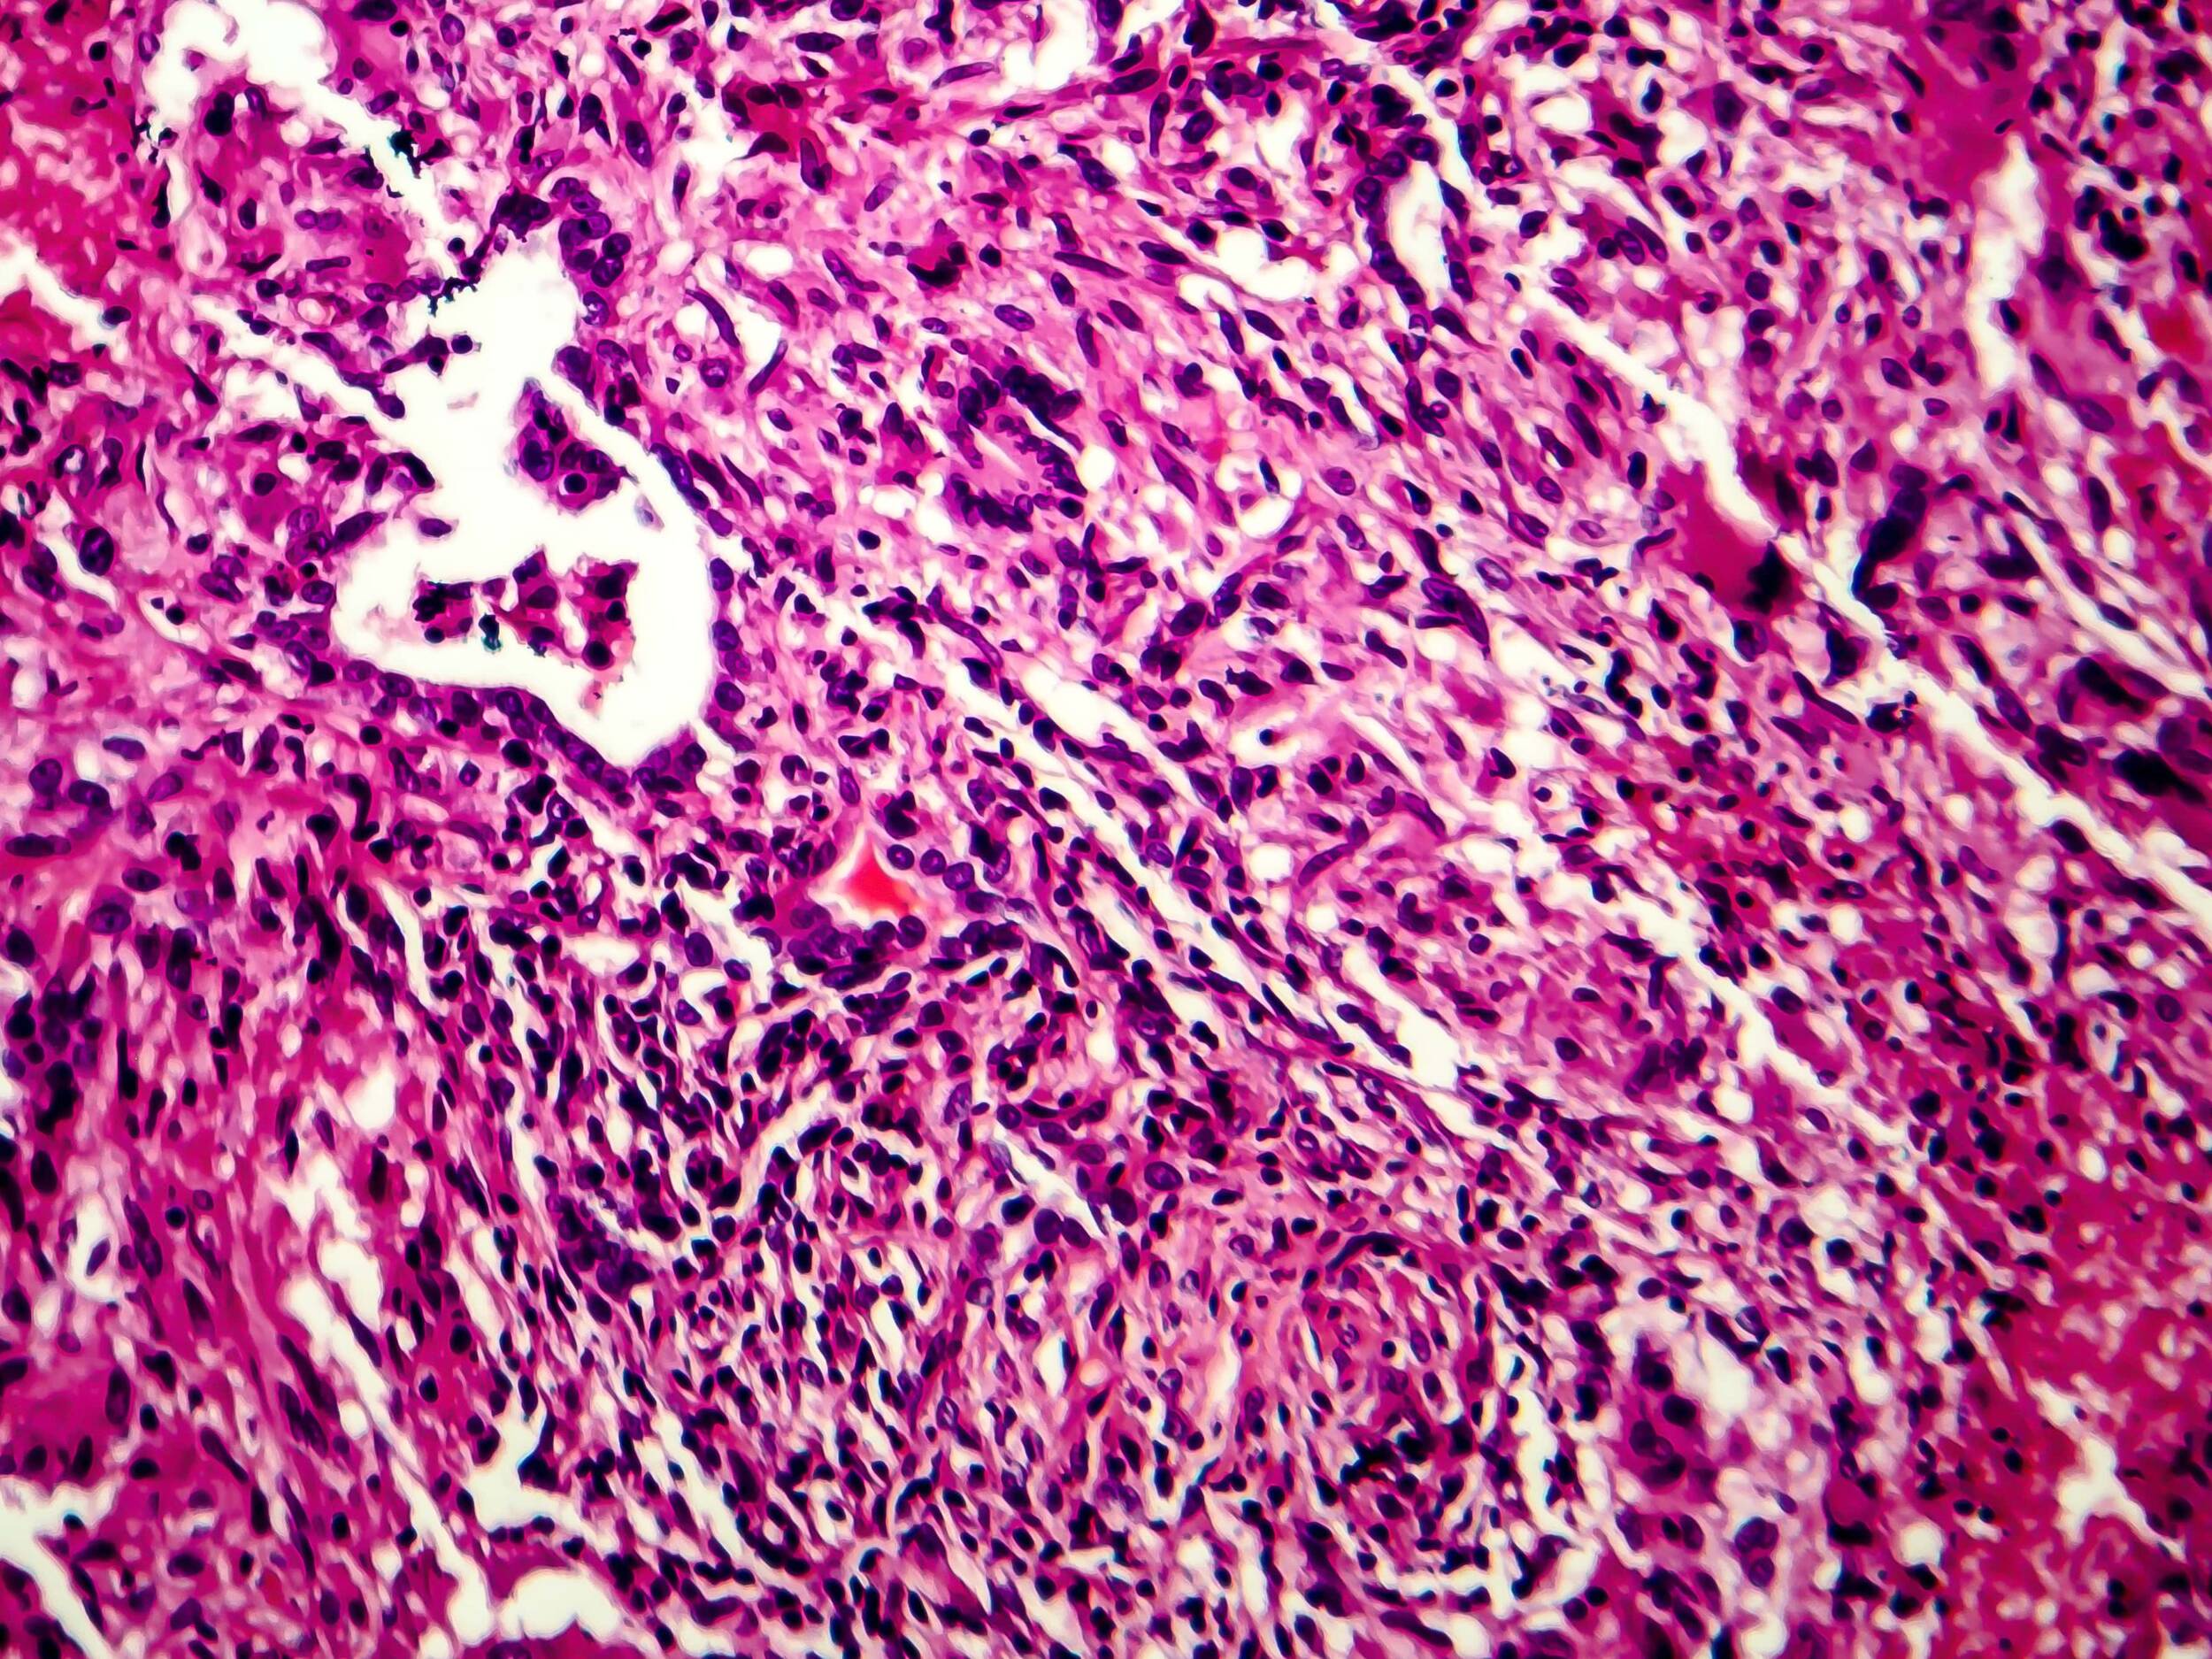

Description: Les bactéries tuberculeuses sont des bâtonnets légèrement courbés d'une longueur de 0.3 à 0.5 μm, immobiles, aérobies (dépendants de l'oxygène) et gram-positifs (coloration de Gram). Elles ne forment pas de spores, en revanche, une sorte de mycélium (filament de type champignon) apparaît brièvement, mais se décompose aussitôt en bâtonnets. Les bactéries se développent très lentement sur des milieux de culture spéciaux pour former des colonies pigmentées, de couleur jaune pâle à orange.

Agents pathogènes: Cultures de l'agent pathogène de la tuberculose humaine.